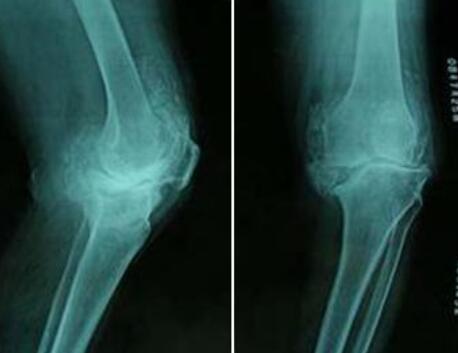

(图:可以看出张先生的双膝关节明显红肿严重)

入院时查:脊柱生理屈度存在,各棘突棘旁轻压痛,双侧肩关节无明显肿胀,局部压痛(+),活动度:外展60°,前屈60°,后伸30°上举100°。双肘关节无明显肿胀,关节周围压痛(+),双肘关节活动度曲140°-5°-0°。双腕关节Ⅰ°肿,关节周围压痛(+)。双膝关节Ⅱ肿,局部压痛(+)。浮膑试验(+)。

(图:从X光片上可看出膝关节已完全消肿,逐渐 )

第二个疗程治疗后,张先生腕关节、膝关节红肿消退,复诊检查时,各项指标基本达到正常。